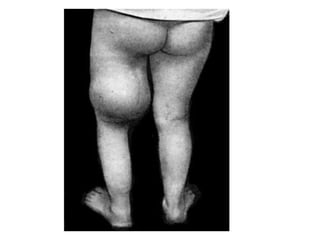

Poliomyelitis

• Poliomyelitis (polio) is a highly infectious disease caused by a

virus. It invades the nervous system, and can cause total

paralysis in a matter of hours. It can strike at any age, but affects

mainly children under three (over 50% of all cases). The virus

enters the body through the mouth and multiplies in the intestine.

Initial symptoms are fever, fatigue, headache, vomiting, stiffness

in the neck and pain in the limbs. One in 200 infections leads to

irreversible paralysis (usually in the legs). Amongst those

paralysed, 5%-10% die when their breathing muscles become

immobilized. Although polio paralysis is the most visible sign of

polio infection, fewer than 1% of polio infections ever result in

paralysis. Poliovirus can spread widely before cases of paralysis

are seen. As most people infected with poliovirus have no signs

of illness, they are never aware they have been infected. After

initial infection with poliovirus, the virus is shed intermittently in

faeces (excrement) for several weeks. During that time, polio can

spread rapidly through the community.